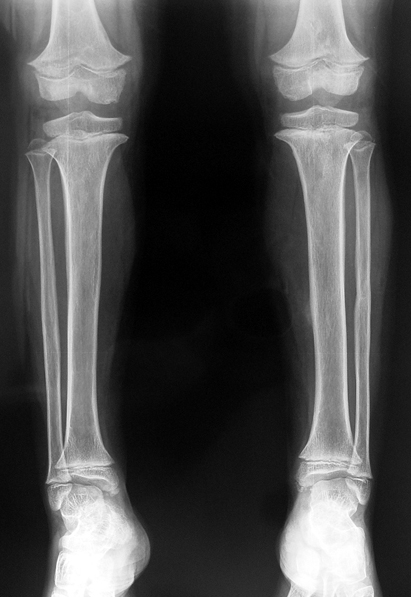

12-14 yaşları arasında Her iki tibiada toplam 10-15cm boy uzatma (iki seviyeli uzatma) Proksimal tibianın varus deformitesini proksimal osteotomi ile düzeltilmesi Distal tibianın varus deformitesi distal osteotomi ile düzeltmesi Distal tibianın varus deformitesi distal osteotomi ile düzeltmesi Boy uzatmanın sonunda lateral kollateral ligamentin gerilmesi Ortalama eksternal fiksasyon tedavi süresi = 8-10 ay